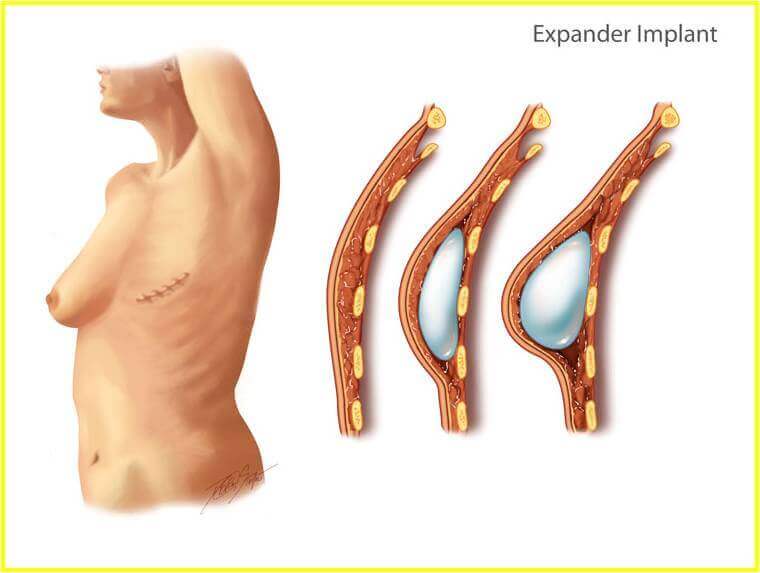

As per reconstruction, nowadays we strongly recommend immediate reconstruction ( at the same time with the initial mastectomy) at least with an insertion of a tissue expander under the muscle on the operated side – step one reconstruction.

6 months after step one and after full expansion of the expander we proceed to its replacement with a permanent silicone implant in equal size and shape with the healthy breast – step two reconstruction.

Step three – Final reconstruction takes place 6 months after step two. Under local anaesthesia and using multiple techniques we create a nipple and areola similar and symmetric to the healthy breast.